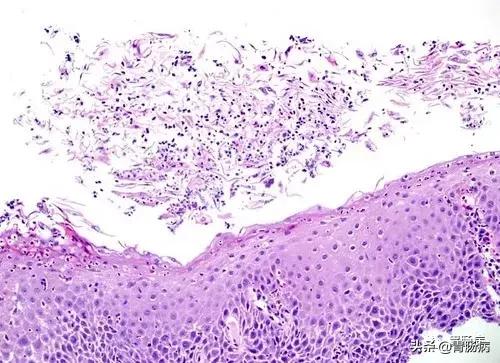

- 进行细菌刷检涂片,可发现白色念珠菌、隐球菌或球状孢子菌等真菌感染、可见炎症、菌丝、成团的芽殖酵母。

霉菌性食管炎病理切片